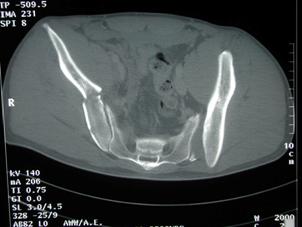

Disjunctie sacro-iliaca stanga Disjunctie sacro-iliaca stanga. Aspect CT

Fractura de coloana anterioara si posterioara Fractura de coloana anterioara si posterioaraAspect CT

asociata cu fractura de aripa iliaca stanga

Fractura de acetabul Fractura de acetabul. Aspect CT